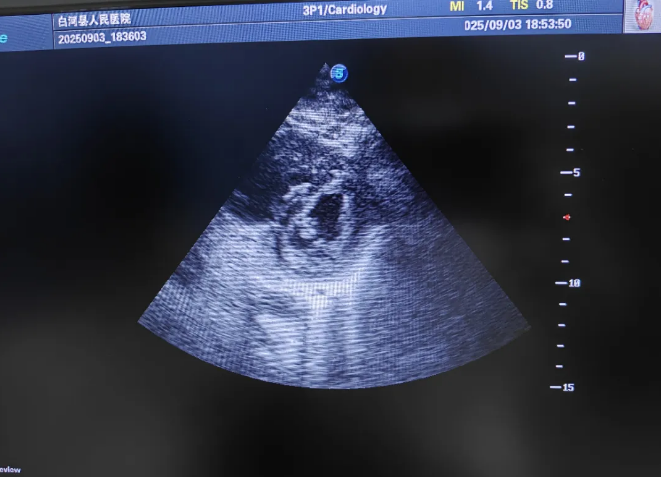

肺超声,排除了大量气胸和胸腔积液;心脏超声,却出现了触目惊心的画面:右心室异常扩大,本该圆润的左心室,在短轴切面上变成了一个扁平的 “D”字。

这是典型的急性肺栓塞征象!结合患者D-二聚体高达16.83μg/mL,以及病史中记录的一条关键信息——“左下肢静脉血栓”,一个危重而完整的诊断链条浮出水面:脓毒性休克合并急性大面积肺栓塞!那条腿里的血栓,脱落了,直奔肺部,堵塞了生命的气体交换通道。